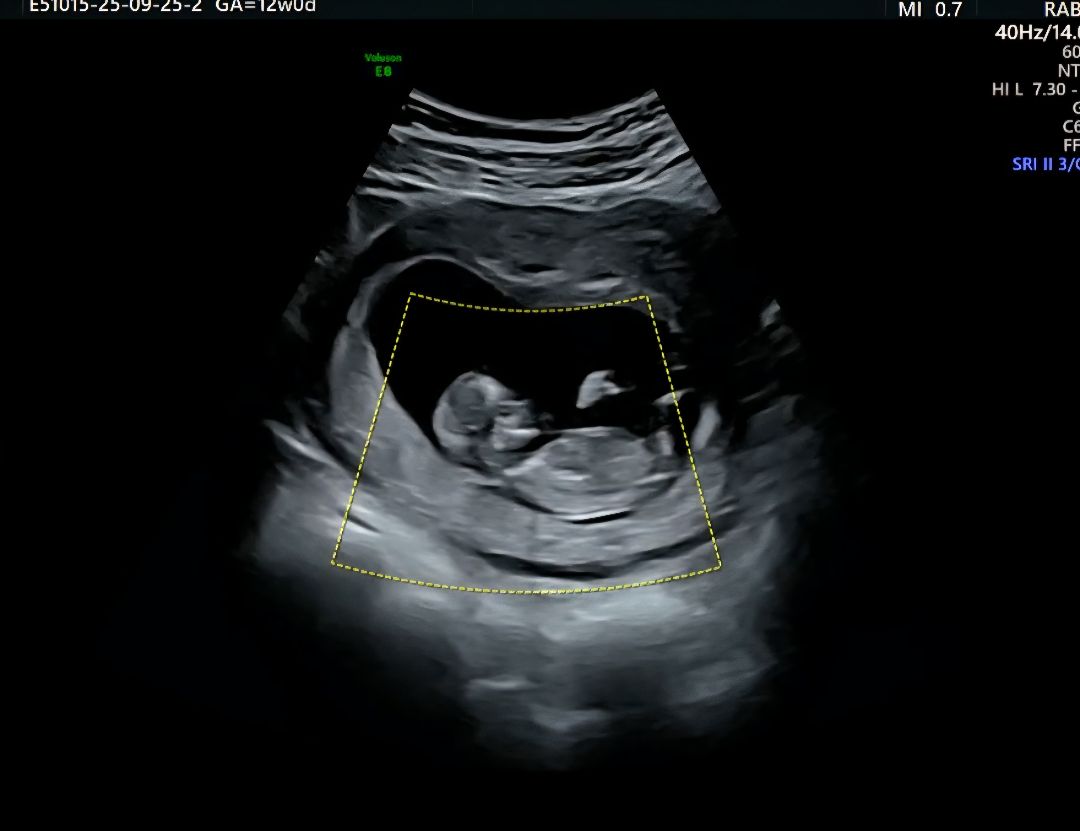

12주 초음파 입니다. 선배님들이 보시기엔 딸일까요 아들일까요?